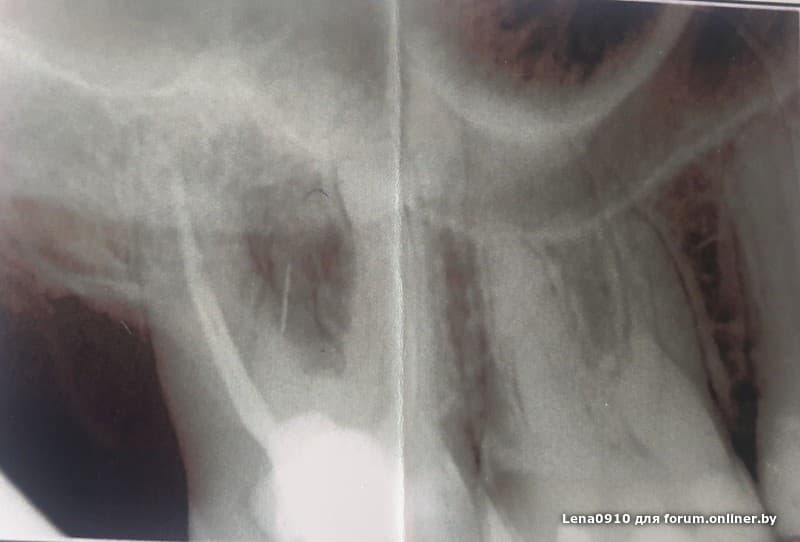

Угадаете где имплант?